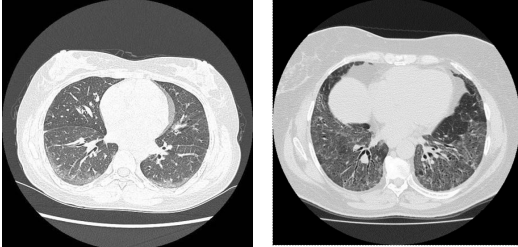

HRCT in COP

consolidation with GG/small nodules Basal/subpleural/peribronchial, can migrate spontaneously solitary mass (less common) septal thickening *reverse halo/Atoll sign, highly specific*

32

What is reverse halo/Atoll sign

focal GG with surrounding ring/crescent of consolidation